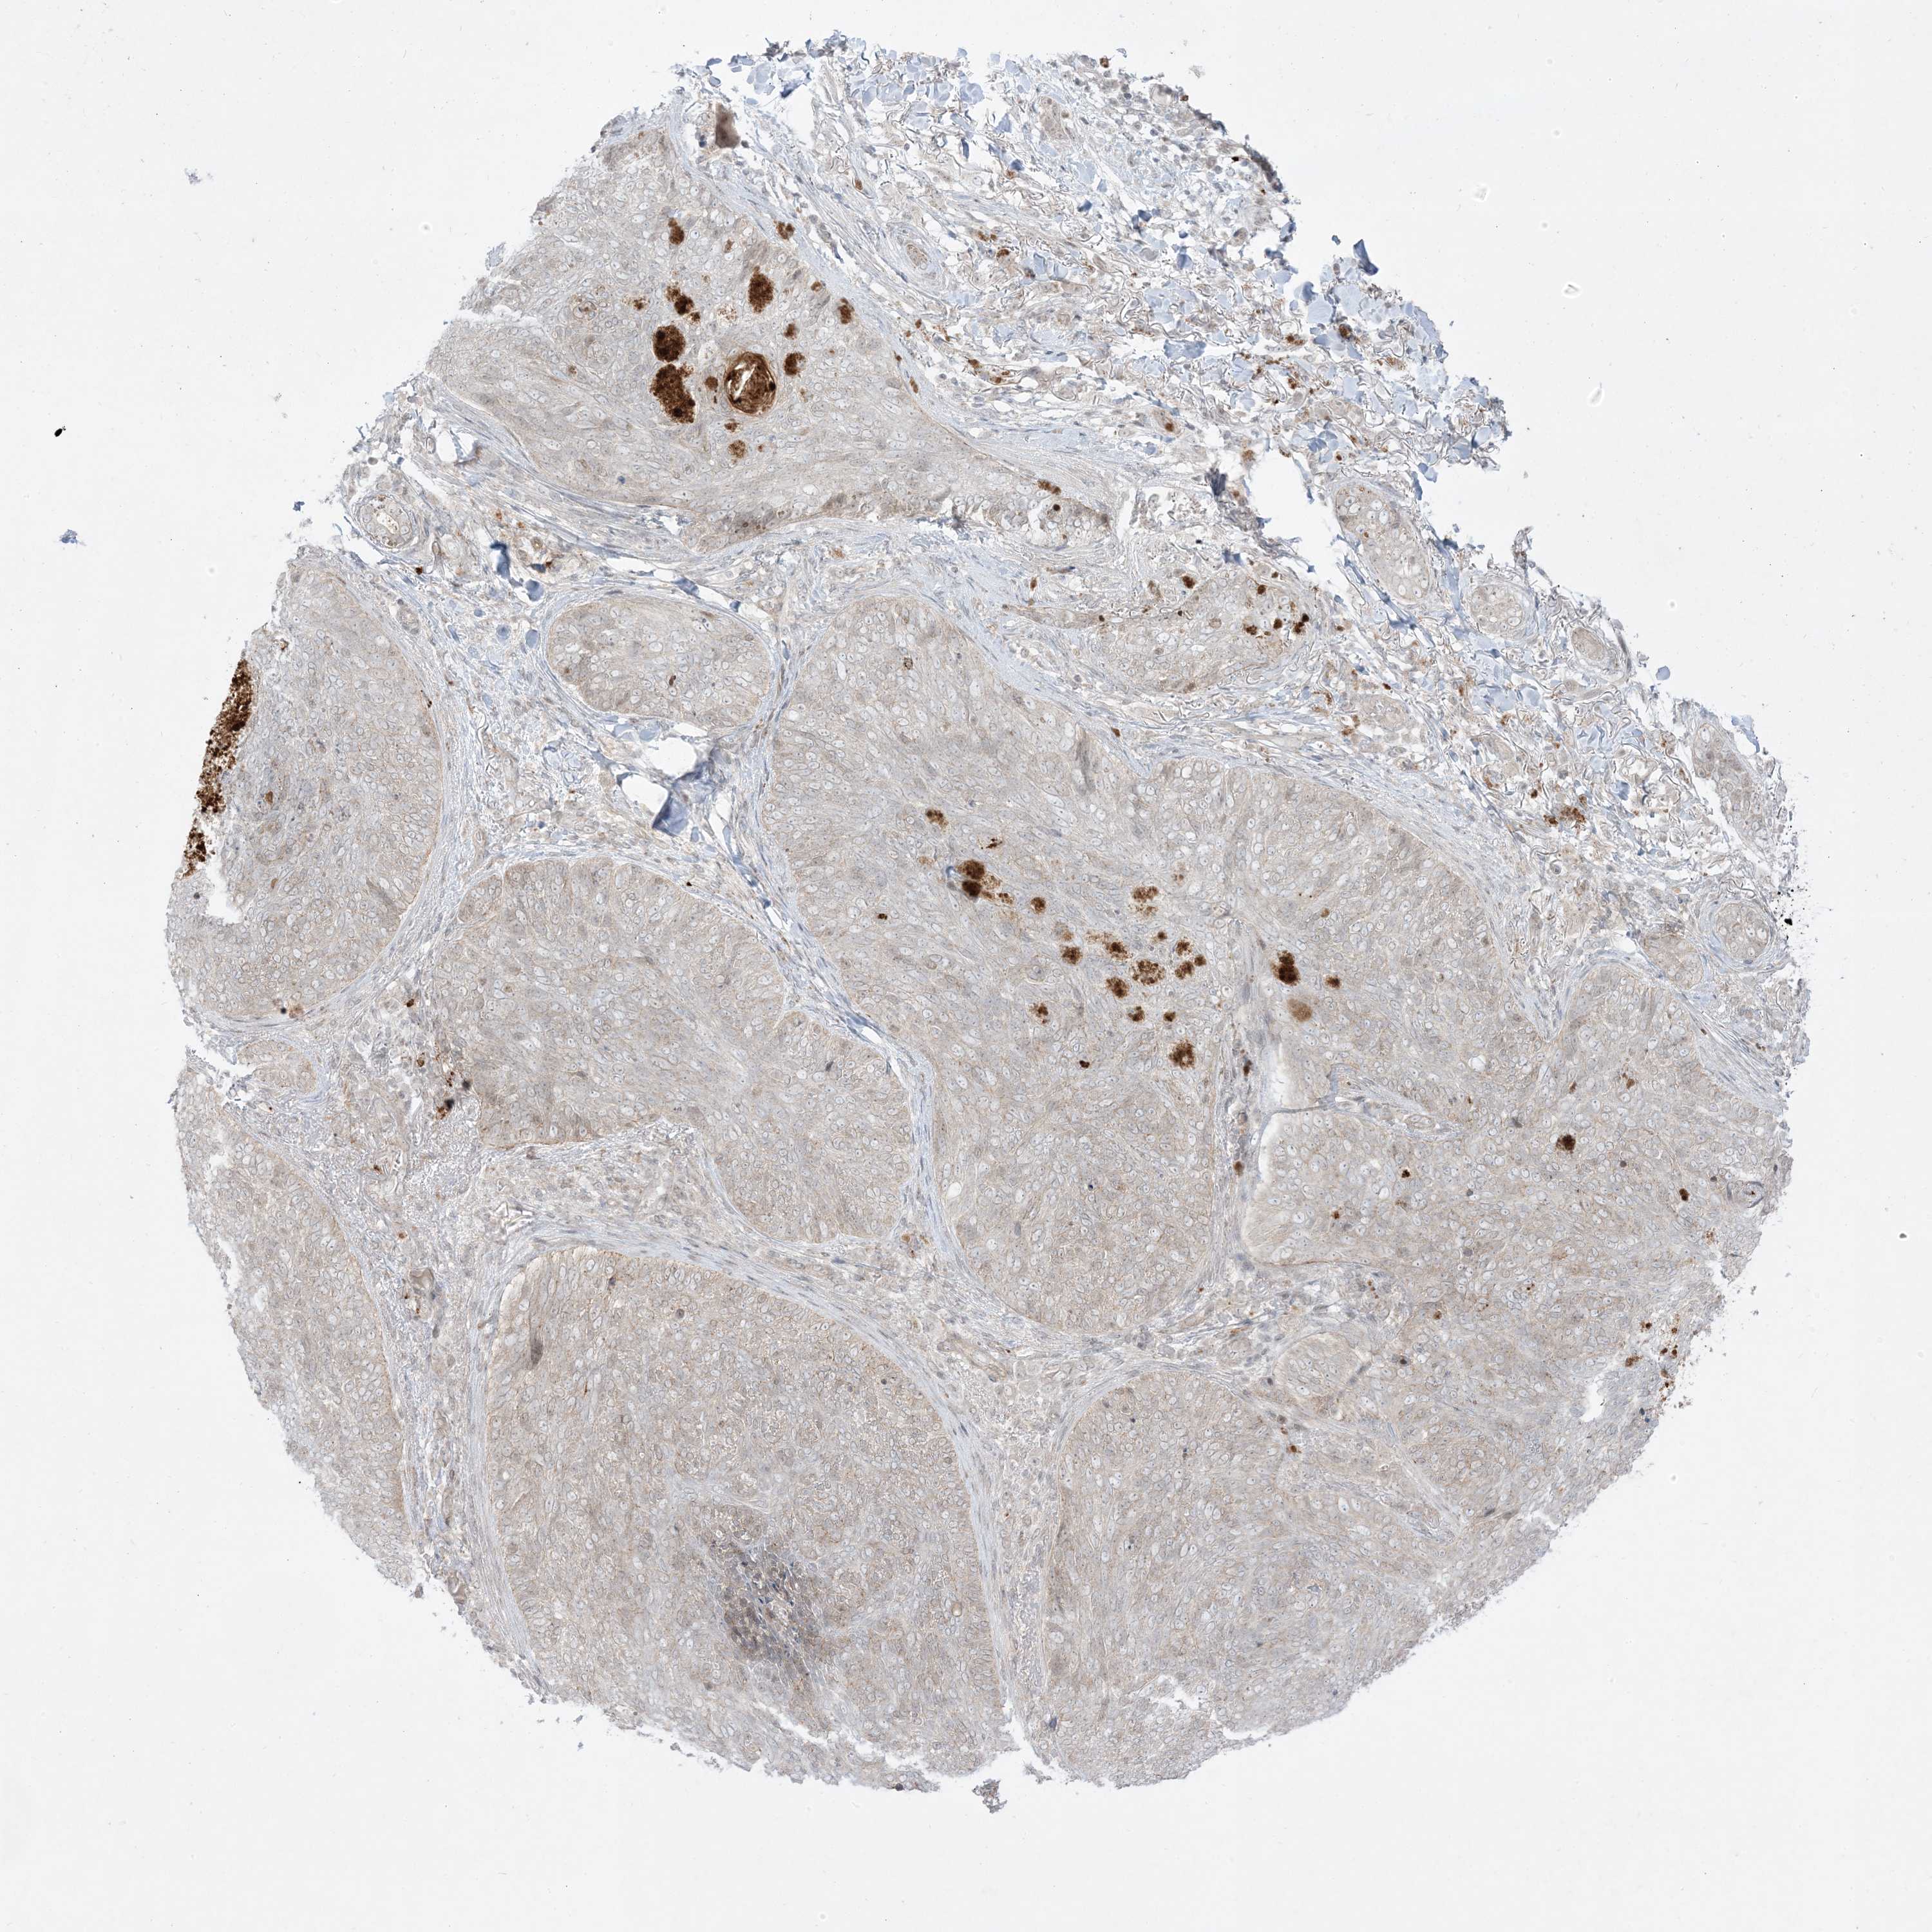

SKIN CANCER - Protein expressioni

A mouse-over function shows sample information and annotation data. Click on an image to view it in a full screen mode. Samples can be filtered based on level of antibody staining by selecting one or several of the following categories: high, medium, low and not detected. The assay and annotation is described here.

Each image is clickable and will lead to virtual microscopy that enables deeper exploration of all samples and also displays staining intensity scores, fraction scores and subcellular localization as well as patient and tissue information for each sample.

Squamous cell carcinoma, NOS